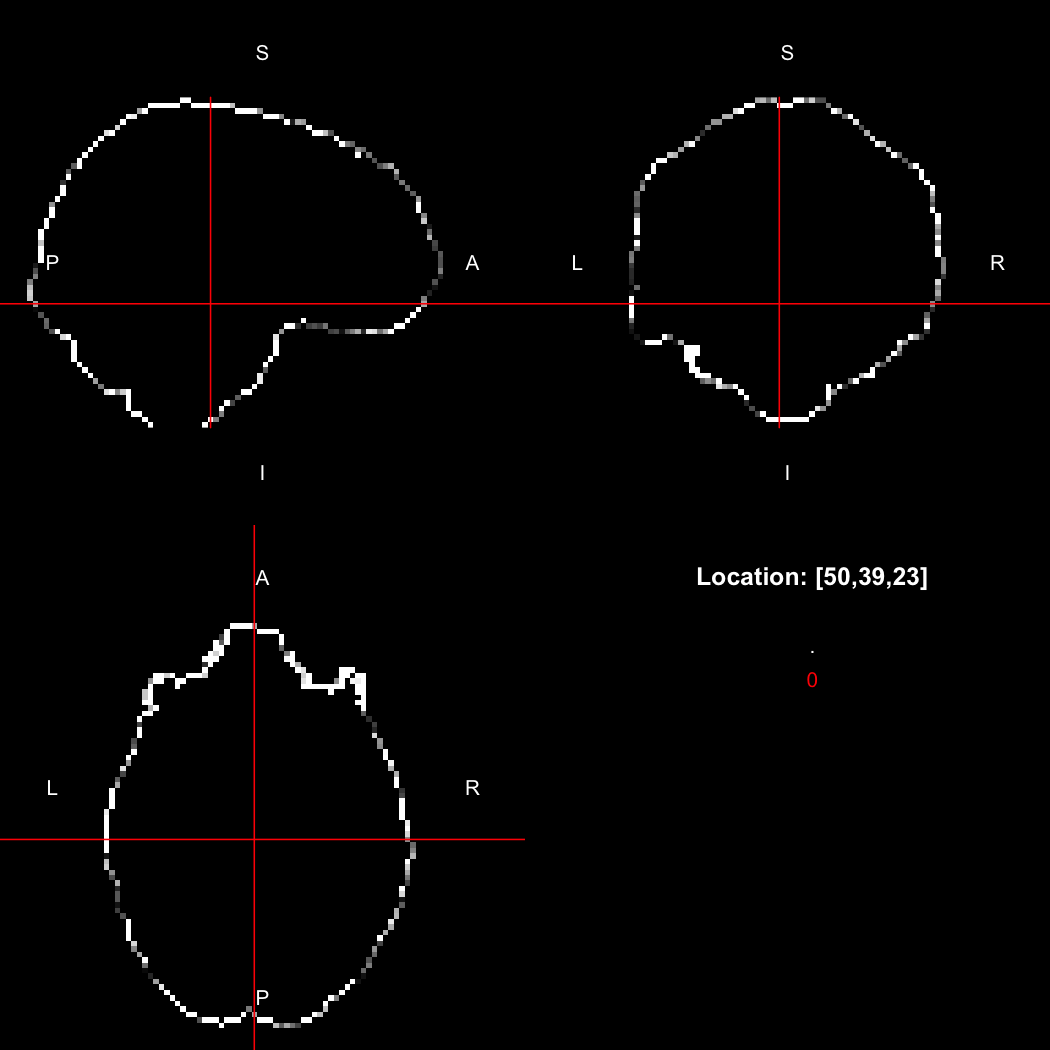

We can also use the RNifti image viewer to visualise the image.

view(image)

plot of chunk original